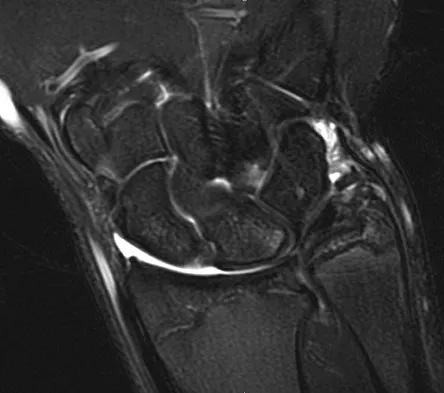

A 35-year-old woman states that she stepped on a piece of glass 6 months ago and reports numbness and shooting pain along the plantar lateral forefoot. She had previously received steroid injections in the 3 to 4 webspace. Examination reveals mild tenderness along the plantar fascia; no Tinel's sign is noted plantar medially and no Mulder's click is noted distally. An MRI scan is shown in Figure 7. What is the most likely cause of the numbness?

Explanation

The MRI scan reveals a laceration through the abductor hallucis musculature and lateral plantar nerve, producing numbness along its distribution. There is no evidence of a foreign body on the MRI scan. Baxter's nerve, or nerve to the abductor digiti quinti muscle, is the first branch off the lateral plantar nerve and impingement of this nerve typically produces a Tinel's sign along the nerve branch deep to the abductor hallucis muscle. Interdigital neuroma would be suggested by the presence of a Mulder's click. A digital nerve laceration would exhibit isolated numbness more distally. Baxter DE, Pfeffer GB: Treatment of chronic heel pain by surgical release of the first branch of the lateral plantar nerve. Clin Orthop Relat Res 1992;279:229-236.